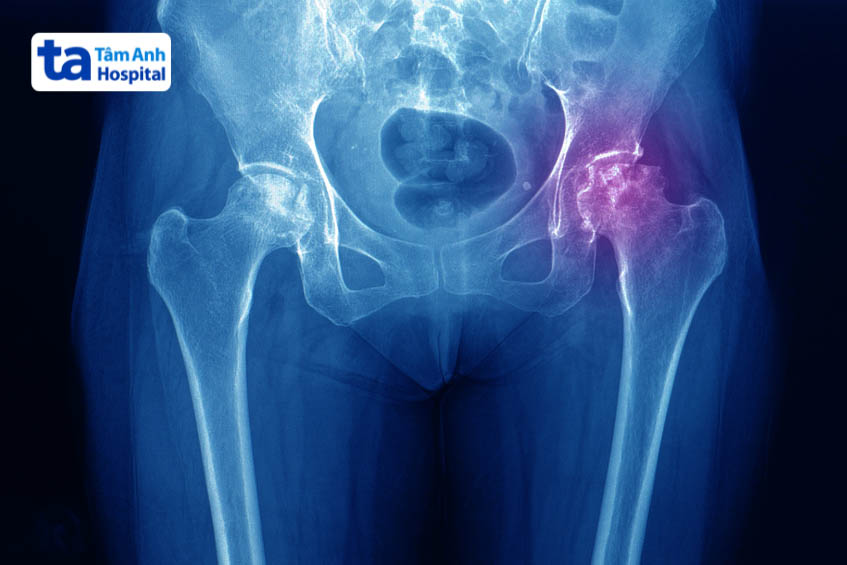

Thoái hóa khớp háng là tình trạng sụn và xương dưới sụn bị thoái hóa, thường gặp ở người già, người vừa bị chấn thương, người mắc các bệnh nền… Khi sụn bị tổn thương, các đầu xương không còn được bảo vệ sẽ cọ xát trực tiếp vào nhau, gây nên tình trạng sưng đau khó chịu vùng khớp háng. (1)

Xét nghiệm hình ảnh cho phép bác sĩ quan sát chi tiết cấu trúc khớp thông qua màn hình chuyên dụng. Từ đó phát hiện các bất thường bên trong xương khớp như gai xương, gãy xương, mảnh sụn hư hại… nhằm đưa ra hướng xử lý phù hợp. Hiện nay, các cơ sở y tế đang ưu tiên áp dụng các phương pháp chẩn đoán hình ảnh gồm: siêu âm, chụp X-quang, chụp cắt lớp vi tính (CT), chụp cộng hưởng từ (MRI).